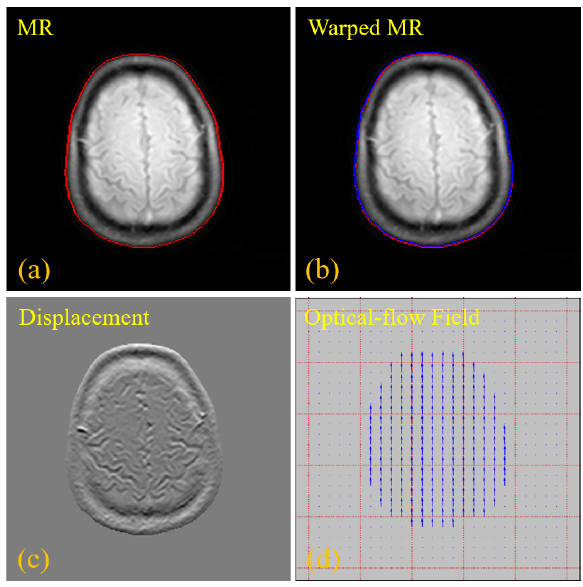

2 基于光流配准的轮廓学习技术,(a)原始输入的MR 图像,红色曲线代表 MR图像的轮廓,(b)配准模块校正后的 MR 图像,蓝色曲线表示配准MR图像的轮廓,(c)配置变换前后的MR图像之间的像素强度差异,(d)稀疏光流场,显示配准预测网络的水平和垂直方向偏移量

由于PET/MR两种模态在纹理上存在显著性差异,直接顺利获得卷积学习这两种模态之间的对齐映射关系非常困难。由此,团队第一时间使用传统的图像腐蚀和膨胀技术来计算PETMR图像的主要轮廓,然后再基于这些轮廓信息来构建光流的偏移量。基于轮廓学习的方法不仅简单有效,而且使得水平和垂直方向偏移量的学习也更加精准。